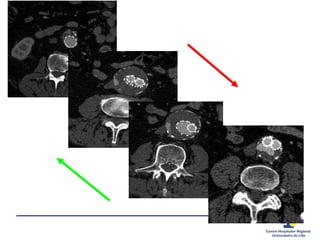

ENDOFUITES type 2

TYPE 2 – Quelle(s) artère(s) alimente(nt) le sac?

Inflow and Outflow

Inflow? Outflow?

outflow

inflow